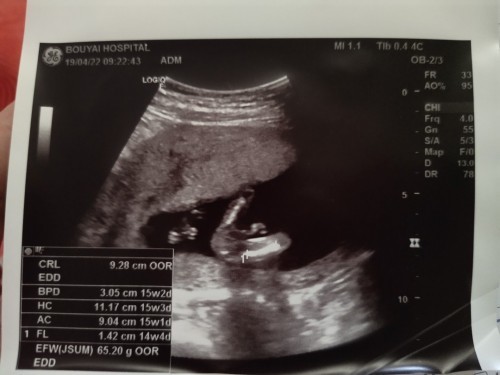

แม่คนไหนพอจะทราบไหมค่ะว่าเป็นอวัยวะส่วนไหนของลูก แอบลุ้นว่าเป็นขากับจู๋น้อง บ้านนี้อยากได้ผู้ชาย😊

เห็นเป็นขาค่ะ แต่แม่เดาว่า ญ. นะคะ